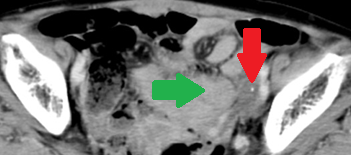

Abdominal CT scan after 2 years. Red arrow – Small remnant of the neoplasm. Green arrow – Small bowel loops (Courtesy Dr. V. Penopoulos)